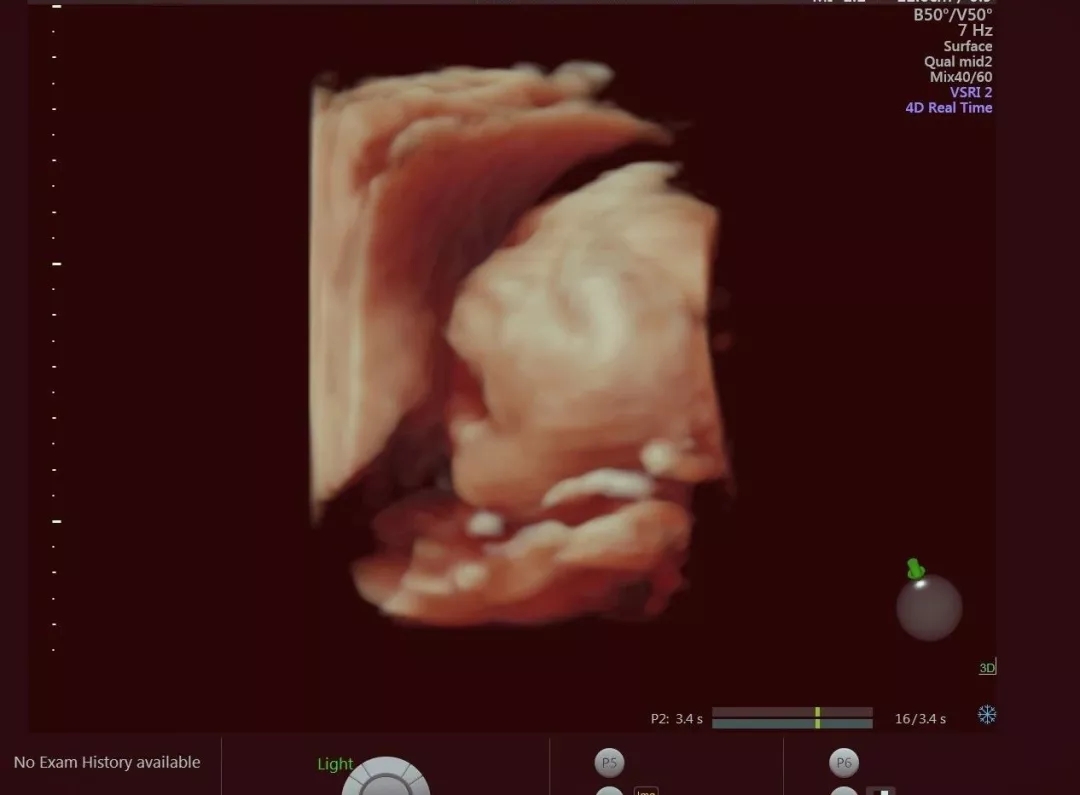

當彩超室醫(yī)生用四維彩超,

將孩子的面部表情呈現(xiàn)出來后,

李媽媽看著畫面直呼神奇!

寶寶得知有人“暗中窺探”

在媽媽肚子里,

開心的張開了小嘴,

樣子超級可愛~

這么多戲,

簡直不能更萌了~

將來肯定是一名小戲精。

四維彩超是在原先的彩超基礎上,

增加了動態(tài)的3D技術(shù),

于是原先圖片格式的寶寶,

變成了動圖格式了!